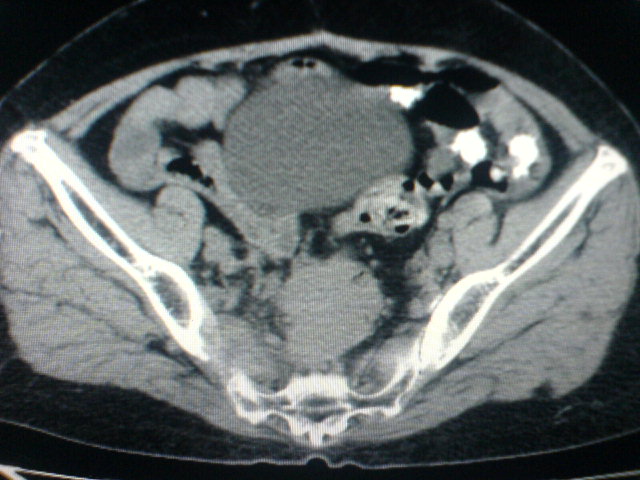

患者为老年女性,肿块最大层面不是位于宫颈,但宫颈偏后方有一囊状低密度影,肿块主要位于乙状结肠及直肠,所以考虑乙状结肠及直肠癌浸犯宫颈可能性大。

患者女性60岁 病史不详

宫颈癌侵犯直肠可能

考虑子宫内膜癌浸犯直肠。

考虑直肠癌侵及宫颈可能;建议增强扫描。

支持考虑宫颈癌上下前后通吃

考虑:直肠及乙状结肠癌侵及宫颈,囊性转移(假性粘液瘤)

支持宫颈癌侵犯直肠。

考虑直肠及乙状结肠癌侵犯邻近结构。